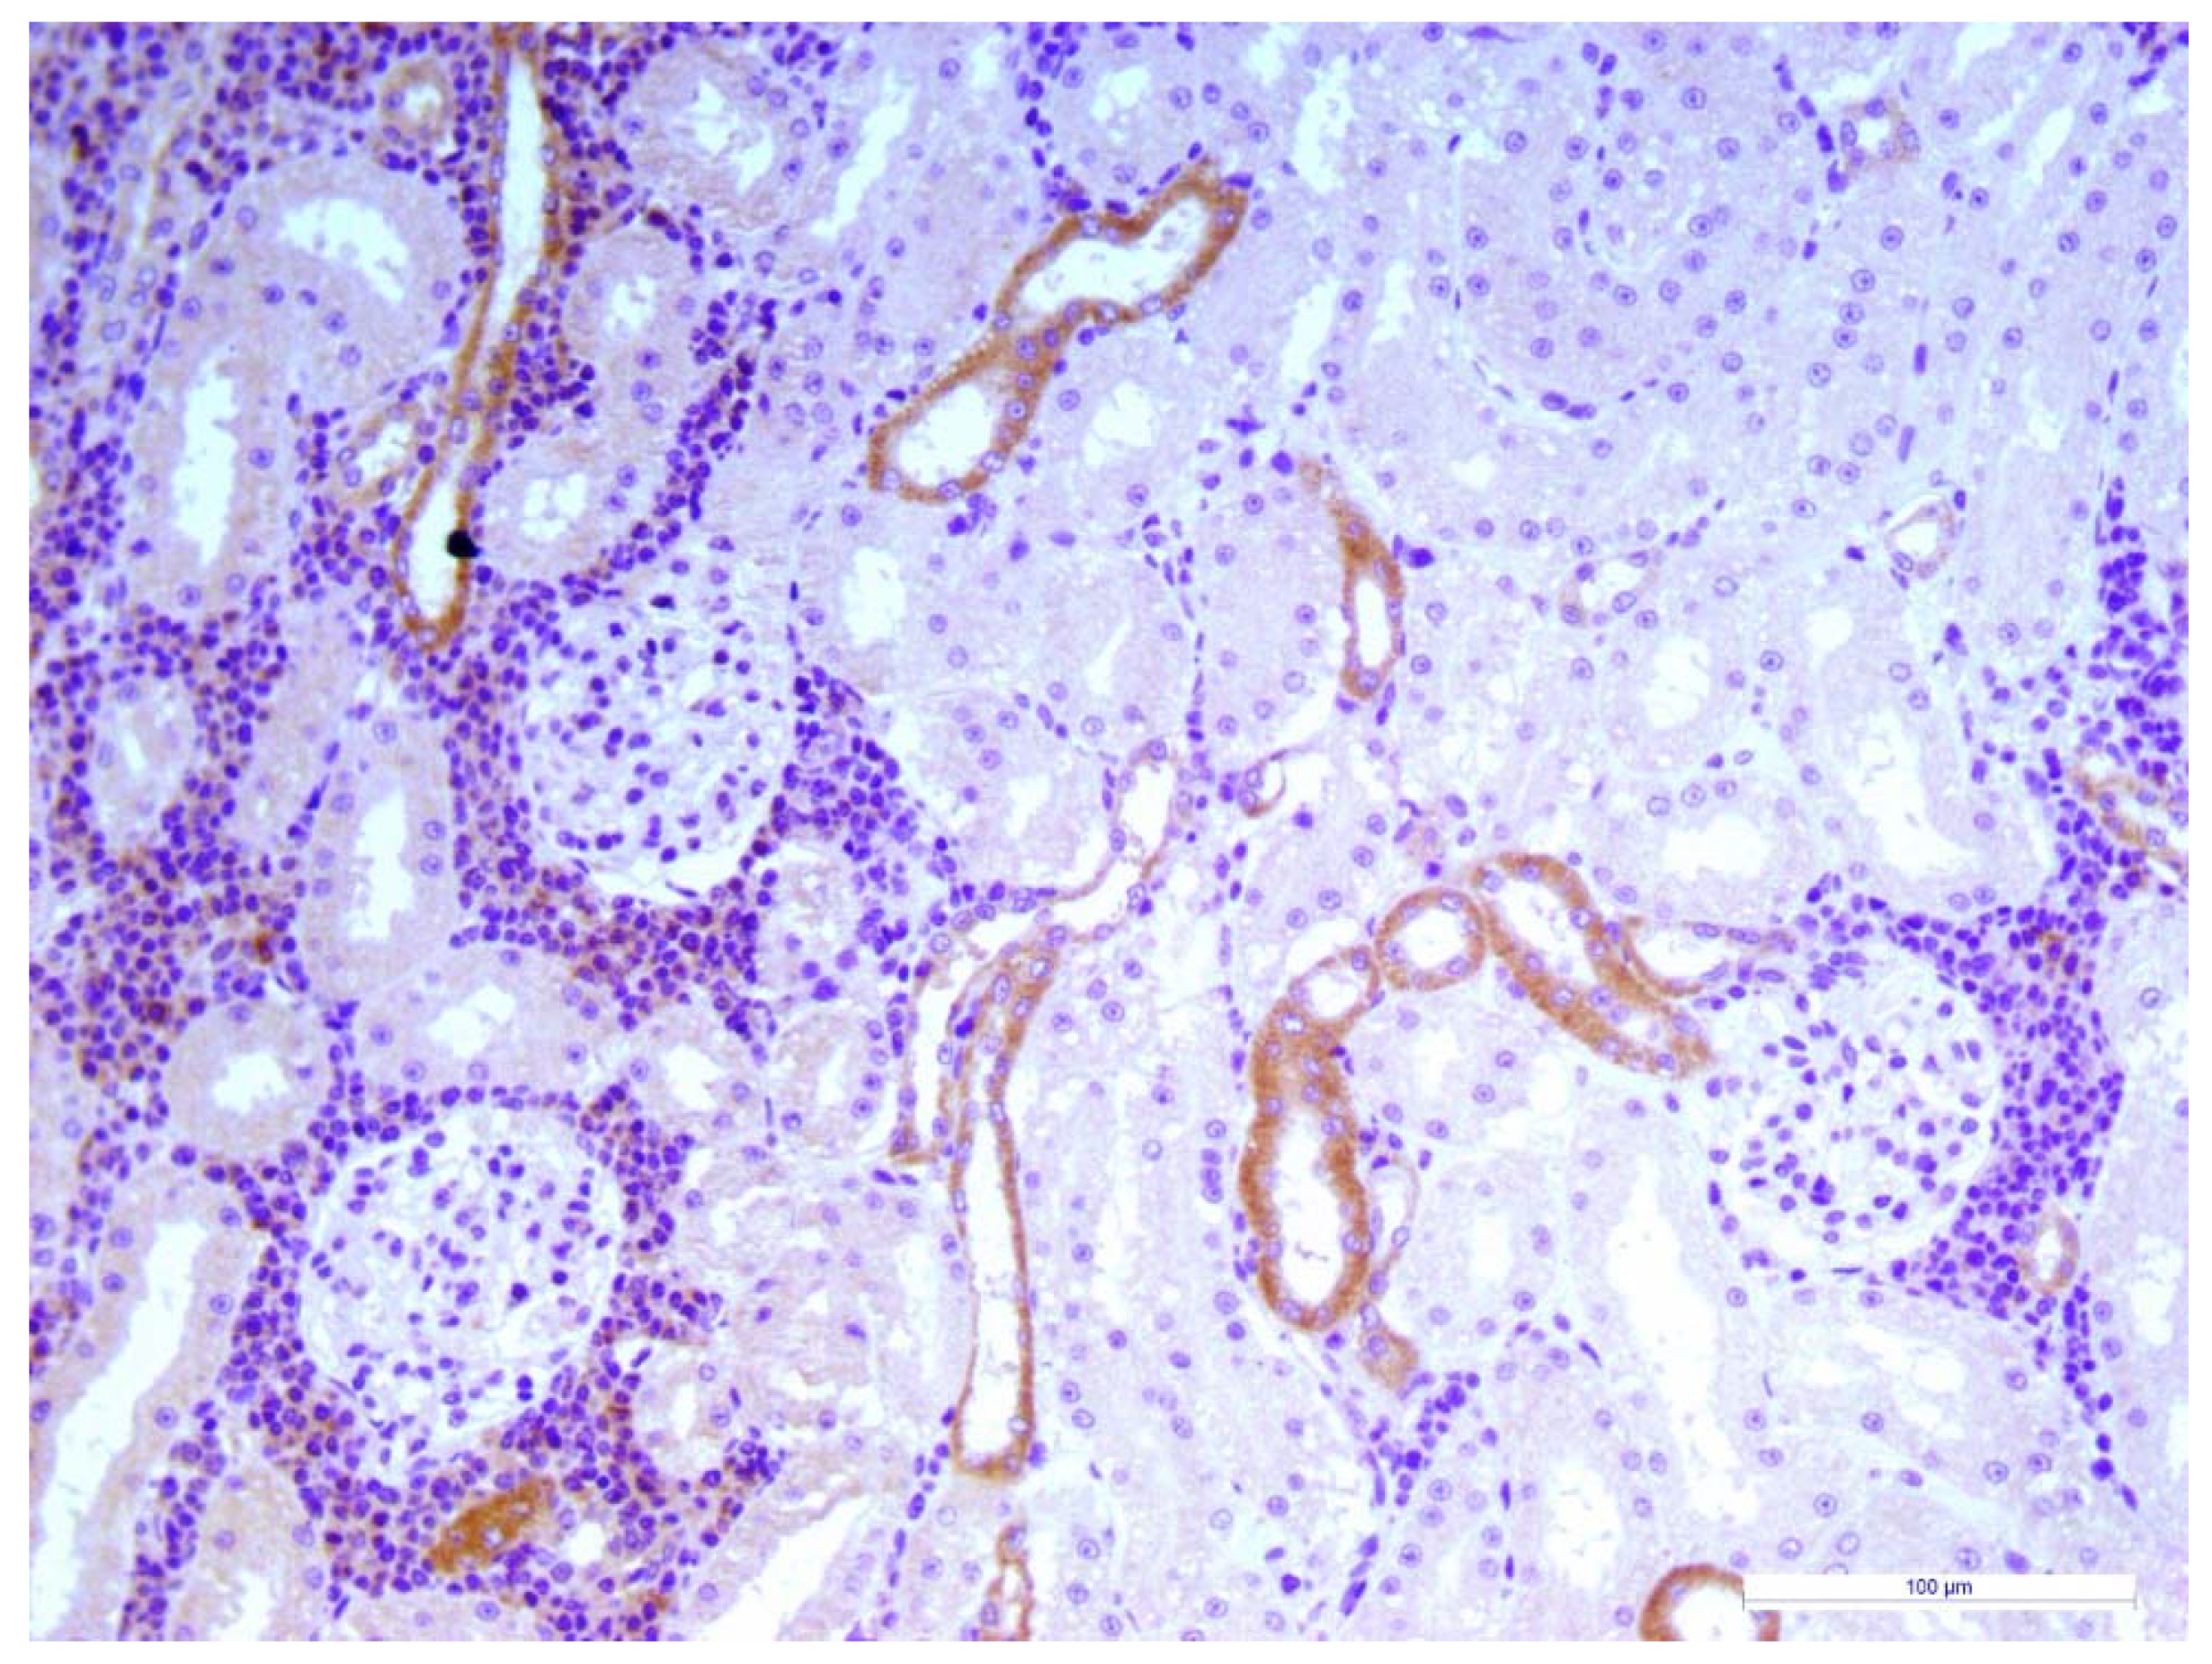

2.3. Renal Histopathology and Immunohistochemistry

4. Discussion